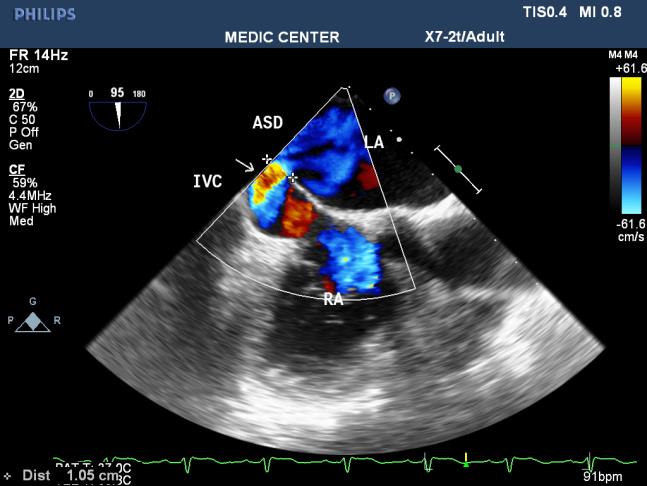

Among 204 Pts with ASD, The secundum defects account for approximately 78%, then primum ASDs 6%, sinus venosus ASDs 12%, multiple shunt ASD 4%, unroofed coronary sinus not seen. 3D TEE can assess the size of ASD and the circumferential rims to select Patients for Transcatether closure. Currently we perform ASD closure limited to ASDs less than 30mm and with at least 5mm of circumferential rims (Table 1).

The X-plan mode can be used to estimate the maximal diameter of defect in two orthogonal planes. Three-dimensional (3D) TEE imaging is an important adjunct to 2D imaging because multiplanar reconstruction ensures that the defect is measured accurately.

Three-dimensional (3D) TEE images can be rotated to demonstrate the defect from the RA or LA side in evaluating the secundum atrial septal defect rims. This improves understanding of their shape and relationships to surrounding intracardiac structures.

Figure 30. SVC sinus venosus ASD with L-R shunting

Figure 31. IVC sinus venosus ASD with L-R shunting